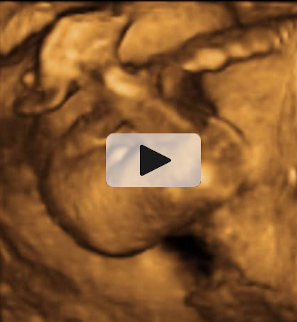

Ecografía: Bebé tapándose la cara con los brazos

En la ecografía en 3D vemos a un bebé de 20 semanas de gestación se tapa la cara con ambos brazos y aprieta los puños. Se trata de un gesto innato que mantendrá en la cuna durante los primeros meses de vida.

Imagen de bebé tapándose la cara con ambos brazos

Ecografía Embarazo 2D y 3D - SEMANA 20